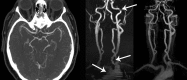

Standard imaging in acute stroke is undertaken with the aim of diagnosing the underlying cause and excluding stroke mimics. In the presence of ischaemic stroke, imaging is also needed to assess patient suitability for treatment with intravenous thrombolysis. Non-contrast CT is predominantly used, but MRI can also exclude any contraindications to thrombolysis treatment. Advanced stroke imaging such as CT and MR angiography and perfusion imaging are increasingly used in an acute setting. In this review, we discuss the evidence for the application of these advanced techniques in the imaging of acute stroke.